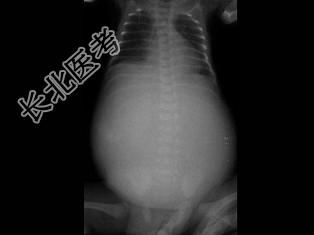

- 单项选择题女婴,7月。经常呕吐, 腹部饱满、膨隆,消瘦。如图所示, 最可能的诊断为 ( )

A、消化道闭锁

B、十二指肠闭锁

C、消化道穿孔

D、肠套叠

E、肠扭转